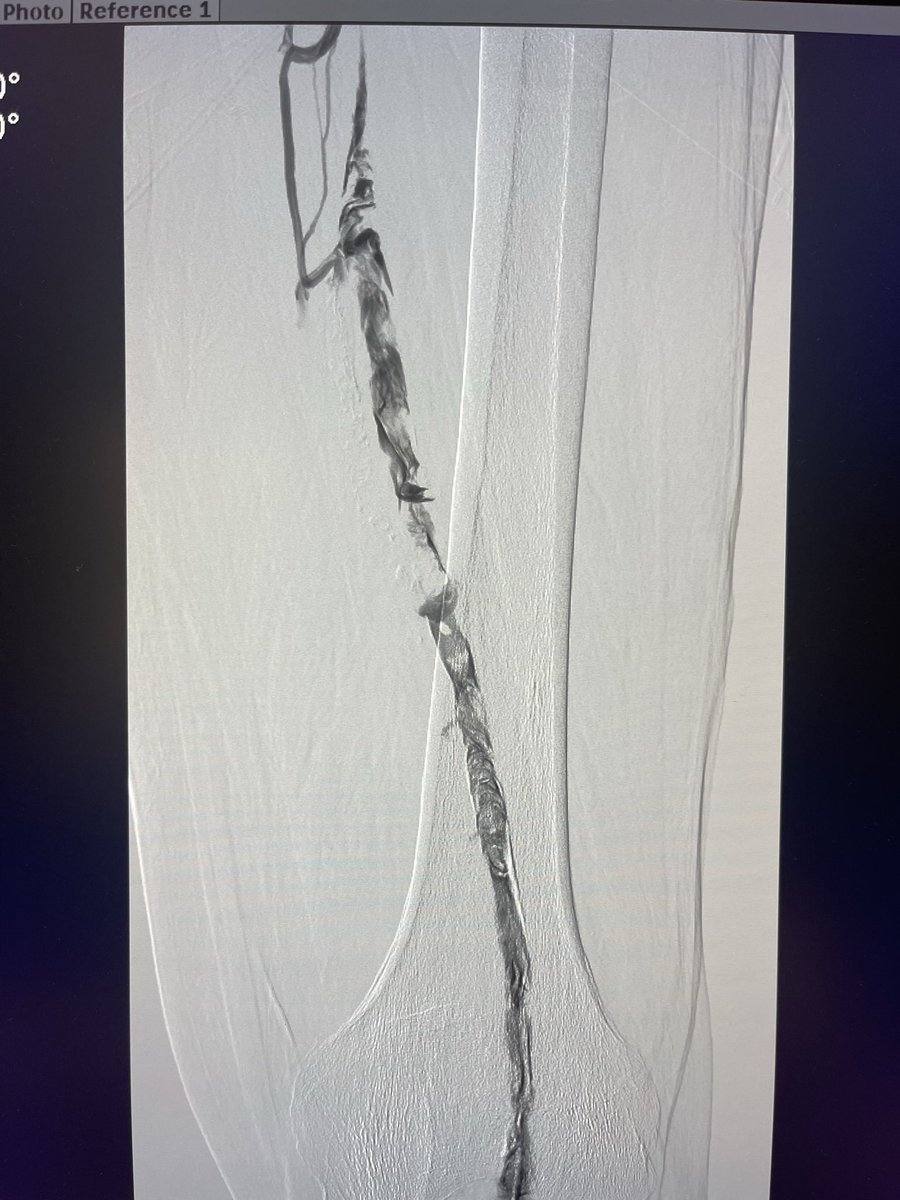

@mazsig @mohamma27915214 @BrettHyattIR @SIRspecialists @SIR_ECS @SIRRFS @cirsesociety @InariMedical @VenousForum This opens a great discussion. We would not have done this case unless the patient presented with phlegmasia. We wait until the patient can be anticoagulated to perform thrombectomy. Our concern is rethrombosis as recurrence off anticoagulation in the acute setting is high.